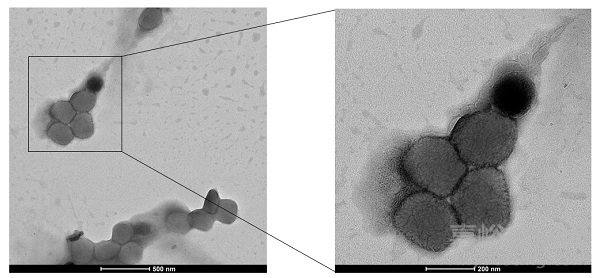

猴痘病毒電鏡圖